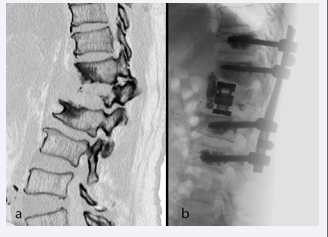

Figure 3 (a) Preoperative CT of a patient with vascular tumor of L1 with  kyphotic deformity.  (b) Postoperative radiograph after embolization, correction by anterior cage  via MIS lateral approach and cement augmented percutaneous posterior spinal  instrumentation.

Perhaps one the most significant developments in MISS is the use of lateral access approach for anterior column reconstruction and sagittal profile realignment in adult spinal deformity (ASD). Open anterior surgeries require extensive incisions and muscle dissections with considerable postoperative complications. Lateral access approach uses a smaller wound with the assistance of retractors and intraoperative neuromonitoring for interbody fusions that lead to more powerful deformity correction in the coronal and sagittal planes. Several studies have now shown that MISS in ASD can achieve good clinical outcomes [17], and may be more suitable for the elderly who cannot undergo large reconstructive surgeries. However, there is still controversy amongst spine surgeons as to the best indications for MISS in ASD corrections (Figure 3)